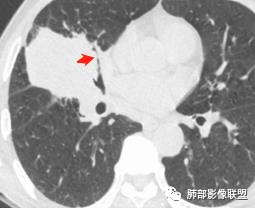

周围小毛刺

小叶间隔增厚?

结节感明显

@吴婧南京市第一医院?吴老师 上叶部分有毛刺,中叶下叶部分有没有毛刺

我也是看到支气管似乎没有堵塞,除外鳞癌

右肺近肺门区跨叶肿块,支气管受压,局部闭塞,肿块分叶毛刺,有较多坏死,局部突入支气管管腔,癌淋,外朝内生长,多发淋巴结肿大,考虑恶性,癌肉瘤?腺癌?腺鳞癌?

@南边?潘老师 上叶部分,分叶,毛刺及癌淋怎么解析